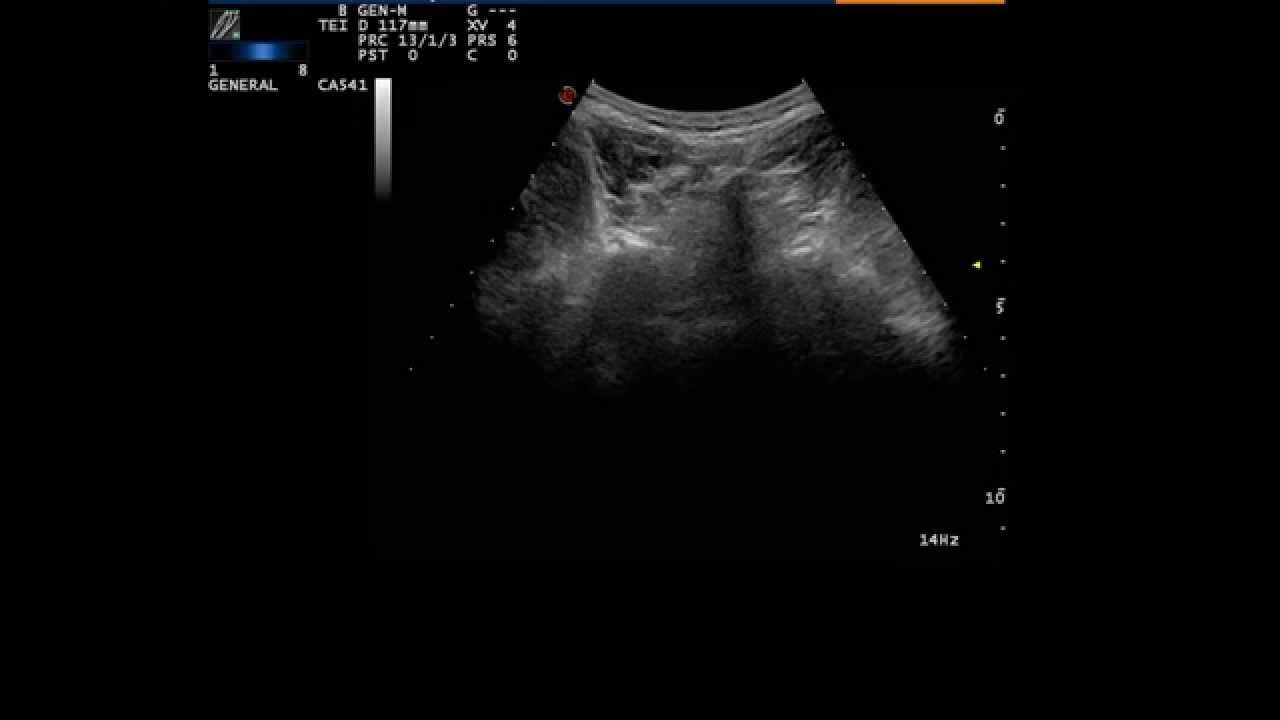

From www.youtube.com

Technique of L5 transforaminal and L5S1 facet joint steroid injection L5 S1 Facet Joint Injections Facet (zygapophyseal) joint injections are performed primarily for the diagnosis and differentiation of facet syndrome and radicular pain syndrome, and are one of the spinal. Facet joint injections work by delivering a combination of a local anesthetic and a steroid medication directly into the facet joint. Facet joint injections are one component of treatment for facet pain, and combining injections. L5 S1 Facet Joint Injections.

Ultrasoundguided facet joint (L5S1) cyst injection , by Prof Murat L5 S1 Facet Joint Injections Facet (zygapophyseal) joint injections are performed primarily for the diagnosis and differentiation of facet syndrome and radicular pain syndrome, and are one of the spinal. From the l5/s1 intervertebral foramen, the l5 posterior ramus runs along the groove formed between the ala of the sacrum and the superior articular process of the sacrum. Facet joint injections are one component of. L5 S1 Facet Joint Injections.